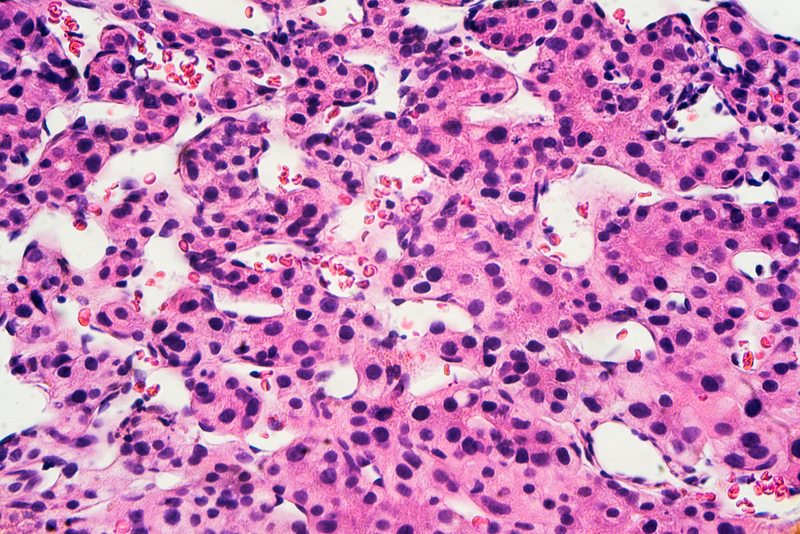

The research published in the journal of CANCER emphasised the need for enhanced efforts to address the growing burden of liver cancer in lower socioeconomic groups. Liver cancer, which in some cases is caused by infection with the hepatitis C virus (HCV), is the most rapidly rising cause of cancer death in the United States.

The team looked specifically at trends in death rates from liver cancer by individual-level educational attainment, HCV-infection status, race/ethnicity, and sex among persons aged 25-74 years. From 2000-2015, the overall liver cancer death rate (per 100,000 persons) increased from 7.5 to 11.2 in men and from 2.8 to 3.8 in women, with the increase largely confined to individuals with less educational attainment.